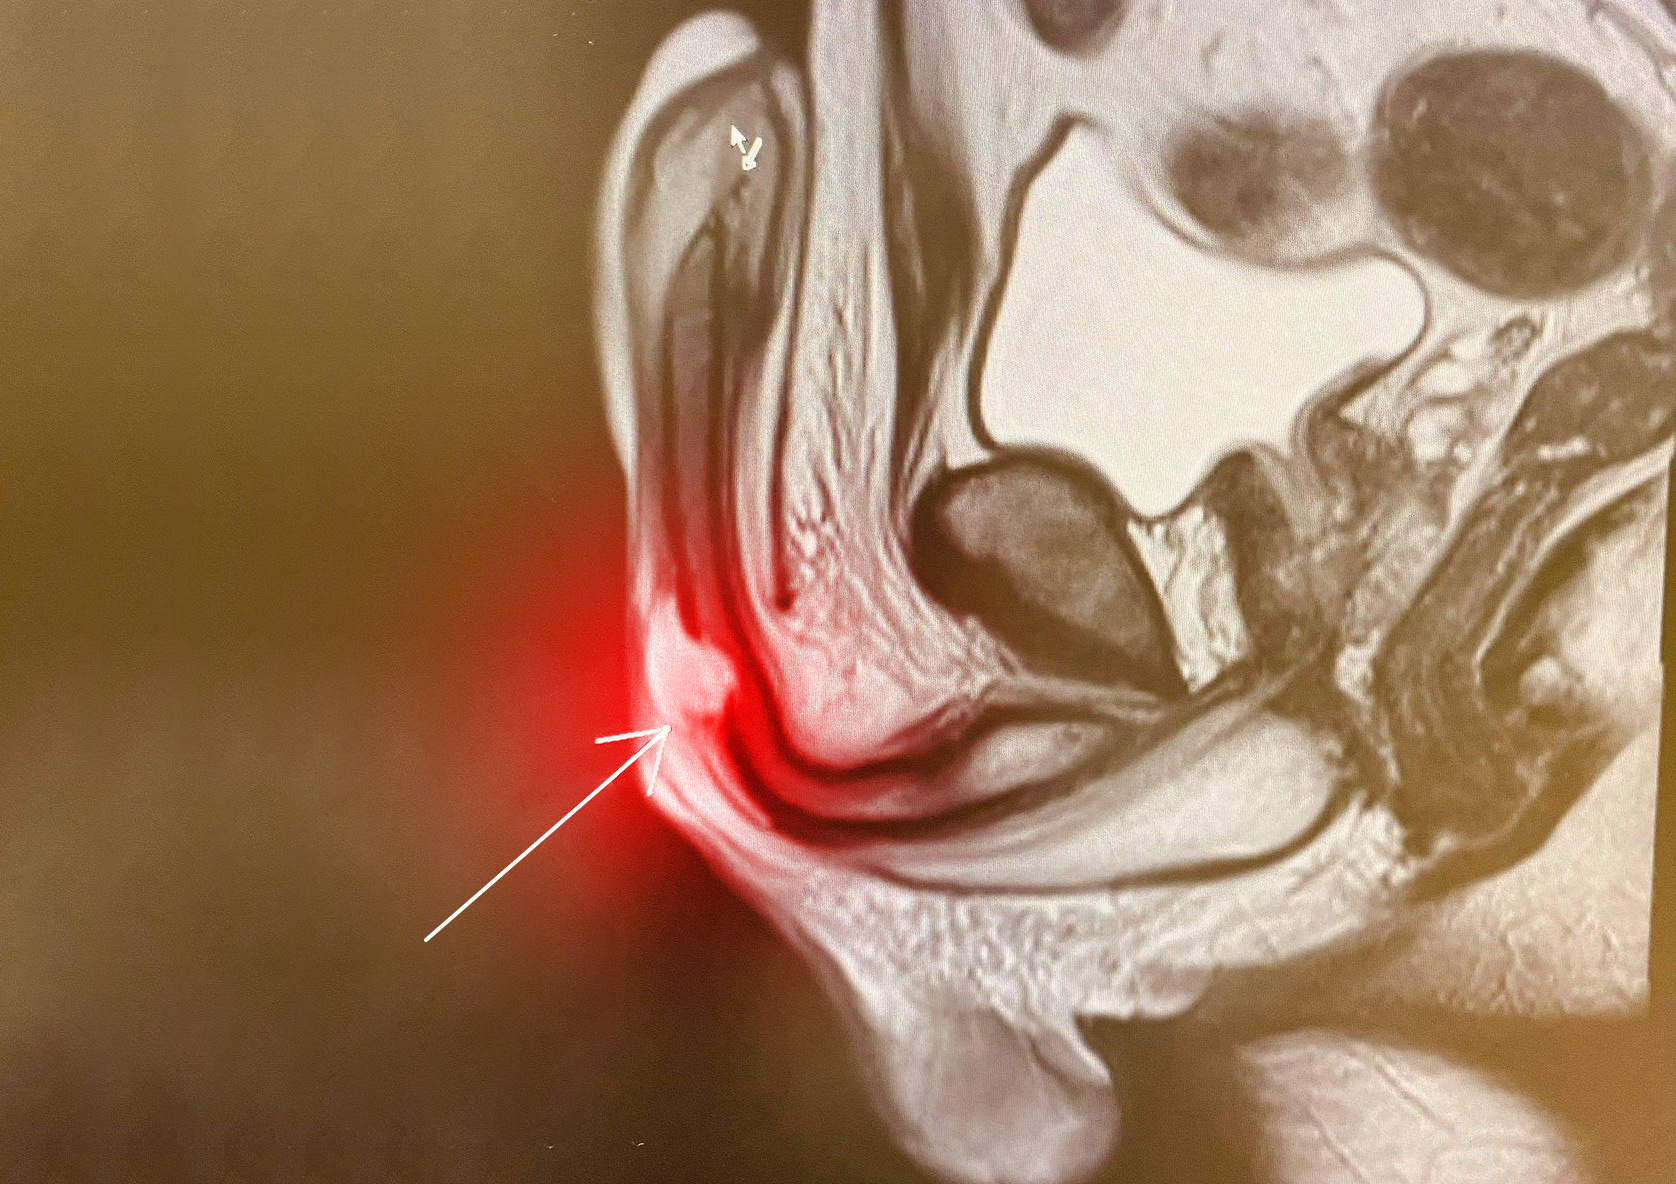

- Chụp cộng hưởng từ (MRI) được chỉ định trong trường hợp nghi ngờ, siêu âm không đánh giá được đường vỡ cân trắng vật hang, ít được sử dụng do tốn kém thời gian và chi phí cao.

Chụp cộng hưởng từ (MRI) có thể phát hiện những trường hợp vỡ vật hang khó